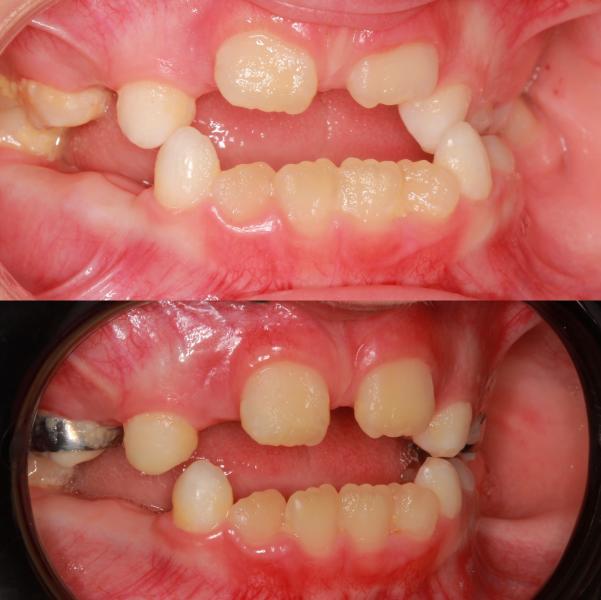

Ребёнок 👧🏼 А 7,5 годиков 🐥😹.

Жалобы родителей «Зубы не прорезываются, неправильный прикус, ассиметрия нижней челюсти».

Лечение решила проводить на несъёмной технике с помощью аппарата #маркоросса

Какие изменения мы получили в ходе расширения верхней челюсти ?

🦷Устранили обратное пер...